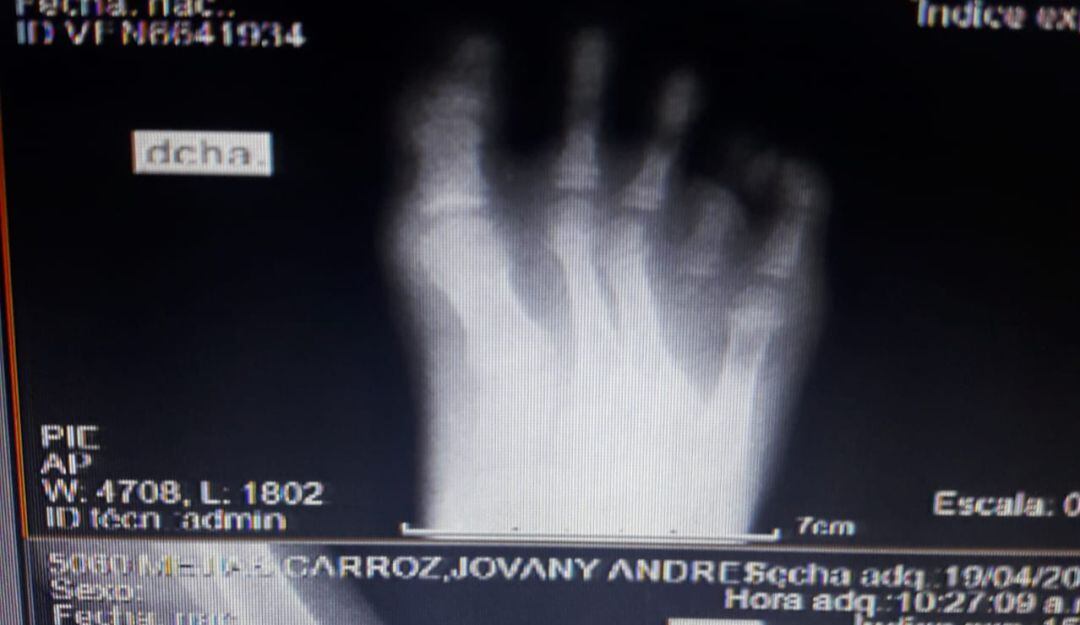

Un llamado enérgico de urgencia hicieron los familiares de Jhovanny Andrés Mejía, un niño venezolano de seis años residente en Cartagena, quien se encuentra a punto de perder un segundo dedo de su pie derecho por demoras en la atención médica para tratar la bacteria presente en los huesos.

La angustia para la familia de este pequeño inició el 15 de octubre de 2020. Ese día, Jhovanny Andrés sufrió un golpe con objeto contundente en su pie derecho y tuvo que ser trasladado a la Casa del Niño donde permaneció durante seis días bajo tratamiento médico. Posteriormente le dieron de alta.

Sin embargo, el niño volvió a recaer por segunda vez el 30 de octubre de 2020 y duró siete días en ese centro asistencial. En esa ocasión fue dado de alta con una prescripción médica y consulta externa especializada pediatría e infectología.

El médico especialista que lo atendió en esa clínica refirió como análisis que el pequeño Jhovanny Andrés debía ser remitido para manejo ortopeda infantil prioritario. Esa solicitud fue hecha el día 30 del mes de abril de 2021 ante el DADIS, la cual hasta la fecha no se ha obtenido ningún tipo de respuesta.

“El paciente ha recibido toda la atención para el manejo agudo de su patología que es una osteomielitis. Recibió durante la estancia hospitalaria atención interdisciplinaria o integral por diferentes especialidades, recibió medicamentos y realización de paraclínicos. Solicitan dar continuidad en el manejo ambulatorio, pero actualmente el Hospital Infantil Napoleón Franco Pareja no tiene contrato para atención de ambulatoria externa de los pacientes que se encuentran a cargo de la Secretaría de Salud Distrital y Departamental”, explicó Beltrán.